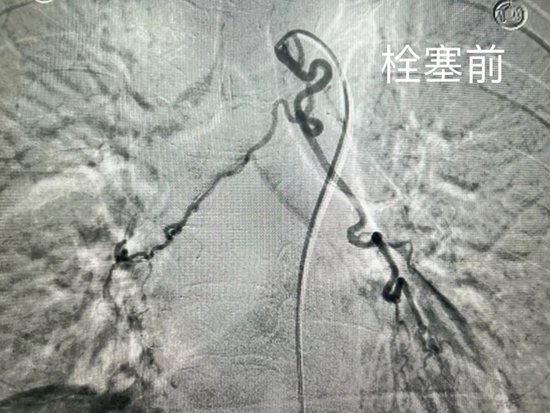

术中,介入团队通过患者右股动脉送入导管,精准找到了肺部出血的源头——异常增粗、迂曲的支气管动脉。随后,利用更精细的微导管将栓塞材料注入到这根血管内部,彻底堵死了出血点。术后造影显示,出血血管已被成功封堵,手术立竿见影。经术后抗炎、止血、化痰等综合治疗,患者恢复平稳,困扰多日的咯血症状得以解除。